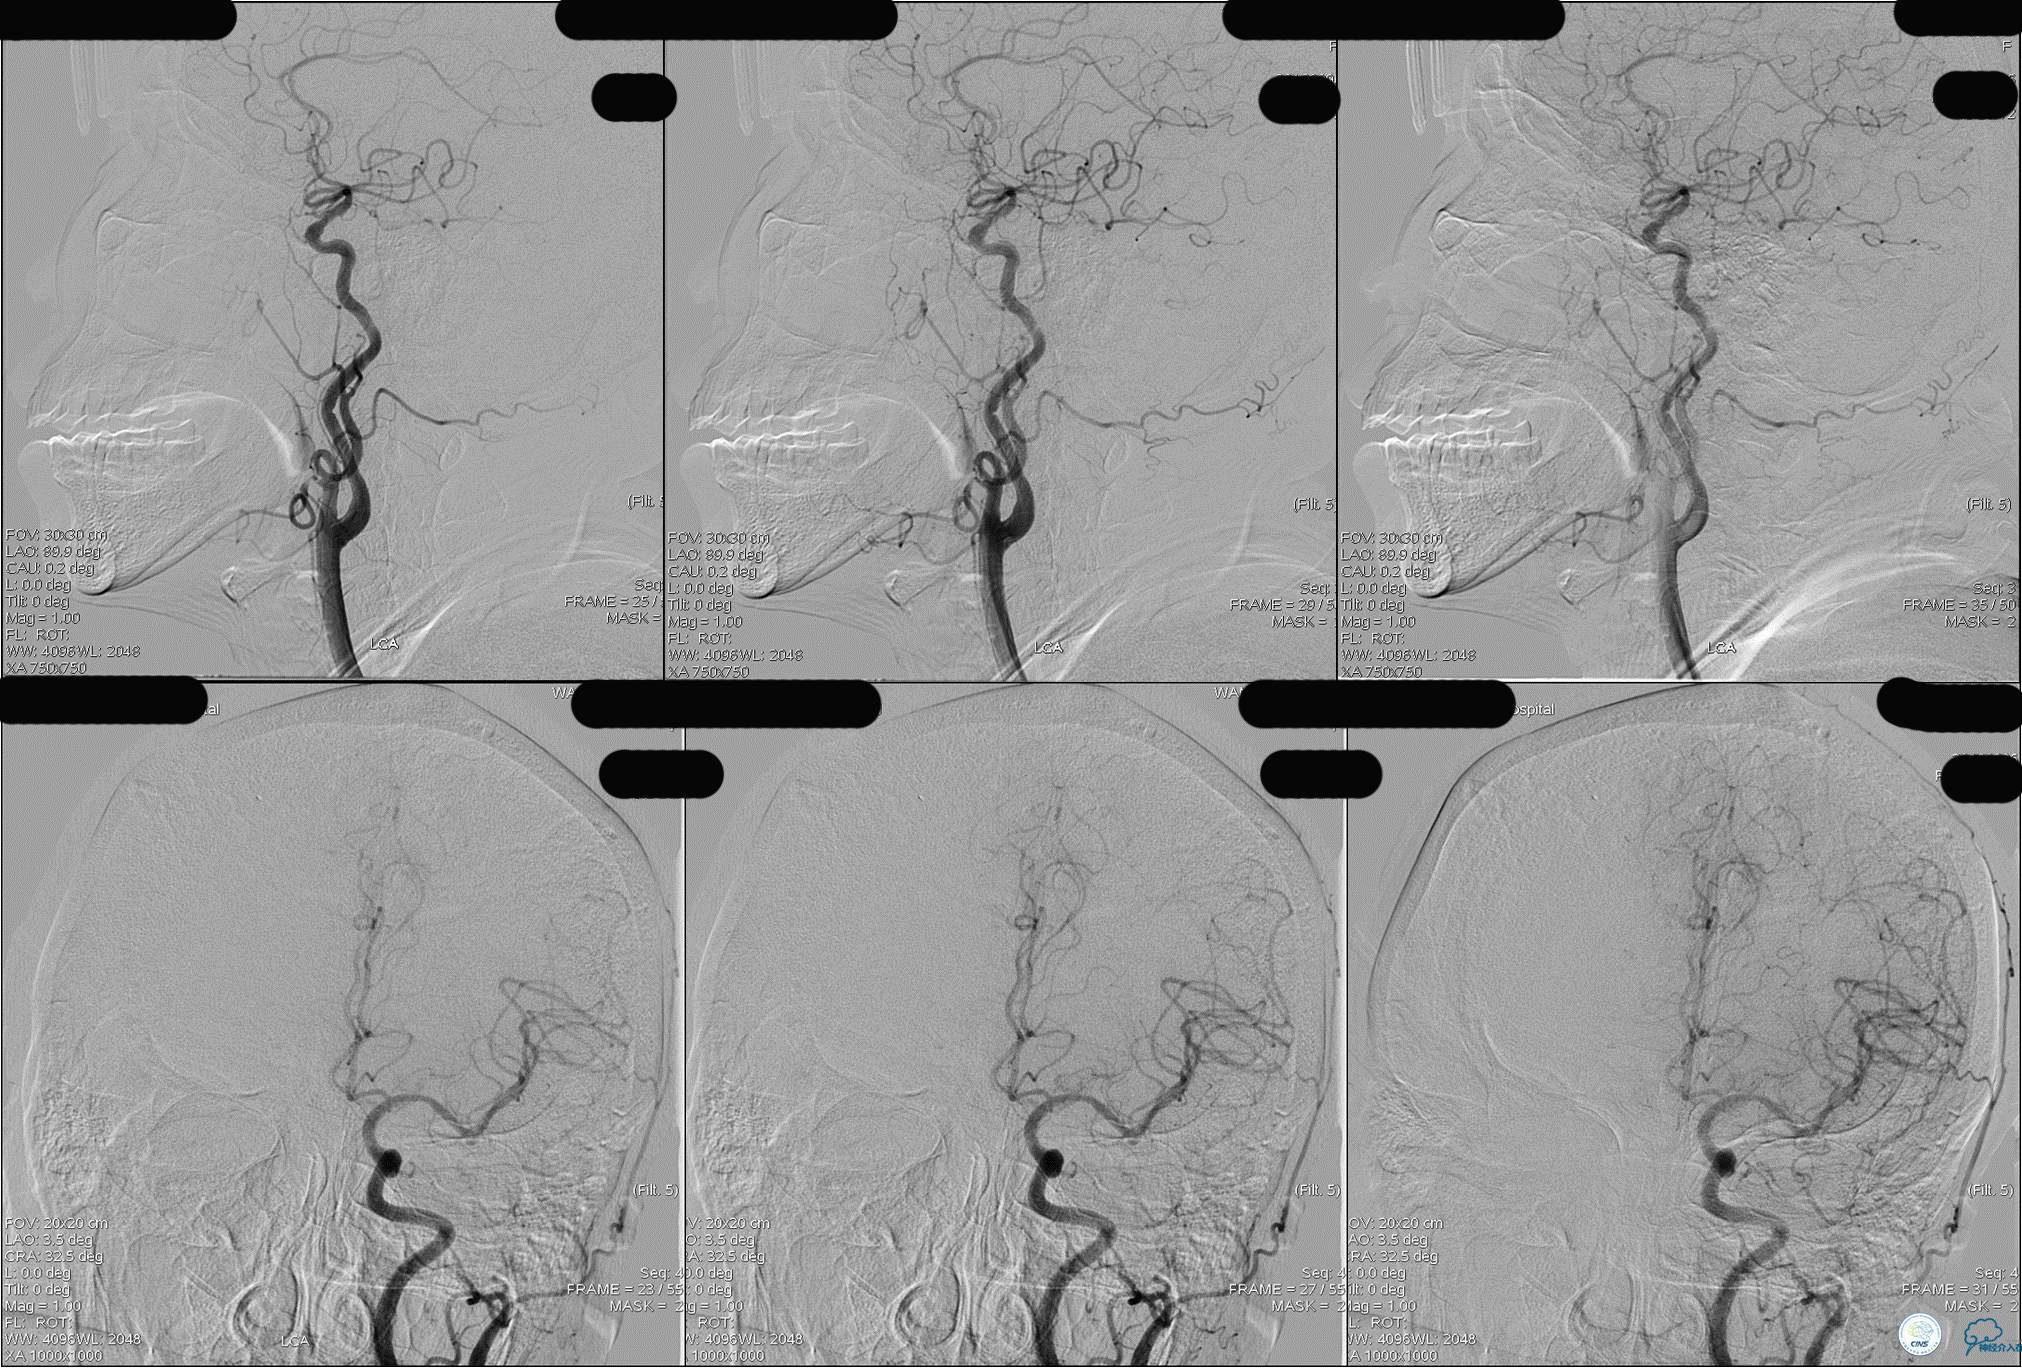

》DSA资料(左侧颈动脉)

》DSA资料(右侧颈动脉)

》DSA资料(左侧椎动脉)

》DSA资料(右侧椎动脉)

》DSA资料(观察30min后,左椎造影)